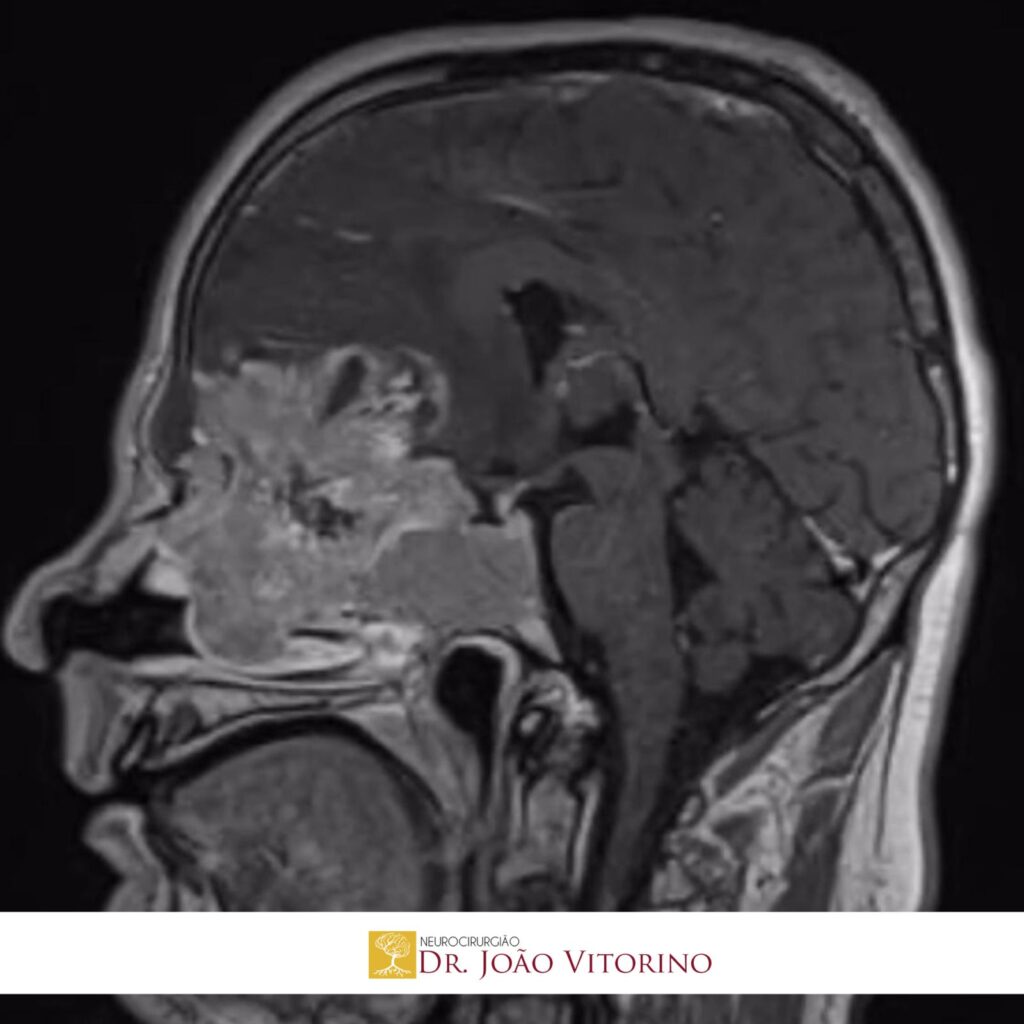

- Tomografia computadorizada (TC) e ressonância magnética (RM), que mostram extensão local e invasão craniana

- Ressecção cirúrgica ampla: muitas vezes por via endoscópica endonasal ou craniotomia quando há invasão craniana

Com o uso crescente de técnicas como neuronavegação, neuroendoscopia e abordagens endonasais ampliadas, a cirurgia tem se tornado mais precisa, reduzindo morbidades e permitindo melhor controle local da doença, mesmo em casos com invasão da base do crânio.